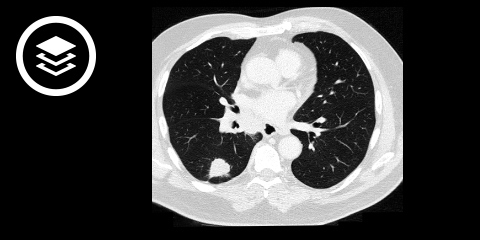

- CT-Thorax mit Kontrastmittel (inkl. Oberbauch)': ist das primäre bildgebende Verfahren zur Beurteilung von:

- Tumorgröße und Lokalisation

- mediastinaler und hilärer Lymphknoten

- Pleura- oder Brustwandinfiltration

- Leber-, Nebennierenmetastasen

CT-Fallbeispiel